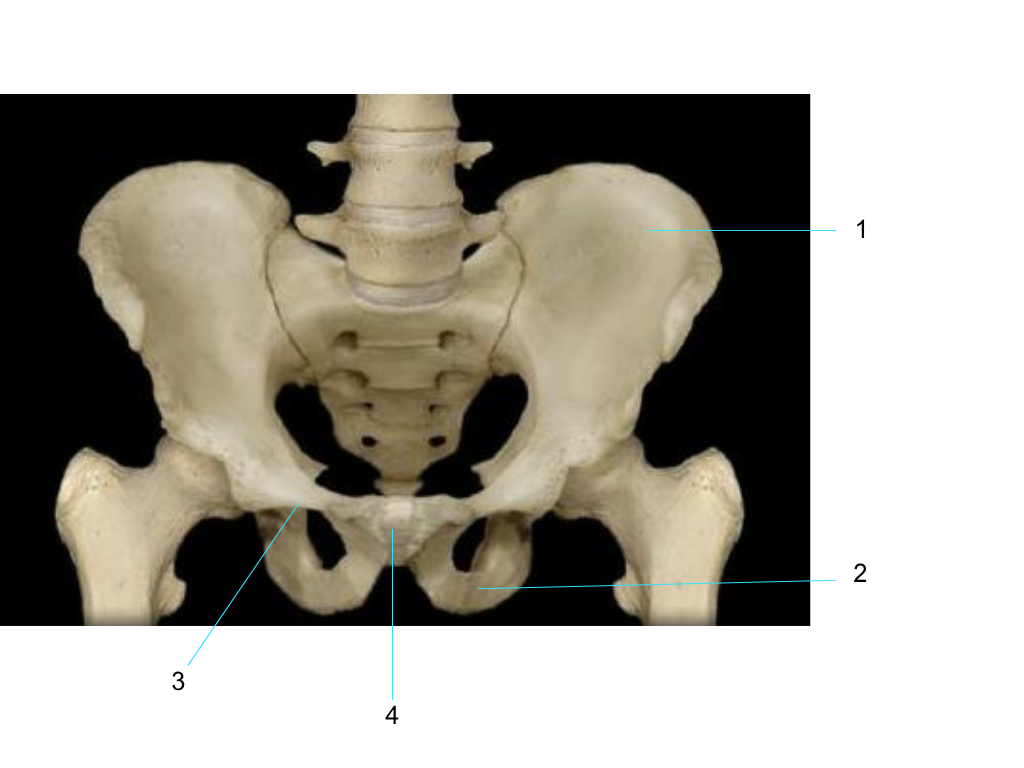

ilium

what is #1 pointing at?

ischium

what is #2 pointing at?

pubis

what is #3 pointing at?

pubic symphysis

what is #4 pointing at?